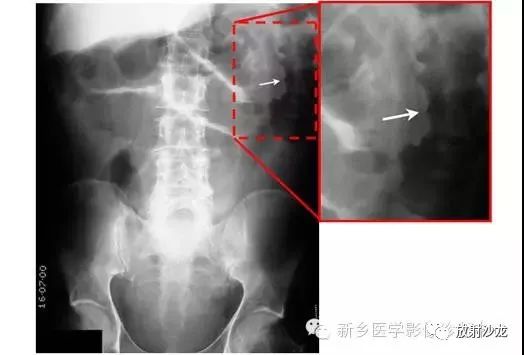

上图腹部平片检查是一6岁男孩,出现呕吐和急性右髂窝疼痛进行的。两个关键的发现在哪里?(提示:通过放射科医生所提供的箭头可以缩小关注点。)

右髂窝多个扩张的小肠襻出现小的钙化结节。小肠袢可与大肠区分开来,因为小肠的环状襞延伸至整个肠壁,而结肠袋只是部分延伸存在。在右下腹(箭头)的钙化结节高度提示阑尾粘连。这个病人开腹手术发现阑尾粘连致小肠梗阻。